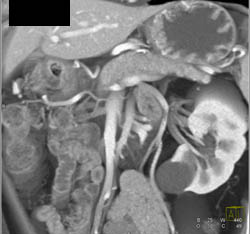

Antral Carcinoma